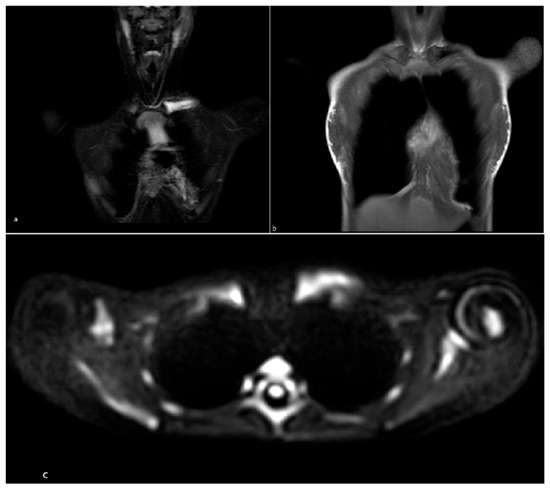

Background and Objective: Clavicular pain and swelling in children can have multiple causes and often require a multidisciplinary approach. We aimed to describe the characteristics and final diagnoses of children with clavicular involvement and to review the literature on this topic. Methods: We retrospectively reviewed patients younger than 18 years who were evaluated for clavicular symptoms at two pediatric rheumatology centers and one pediatric oncohematology center. These data were then descriptively compared with findings from 63 patients reported across 7 published articles. Results: Twelve patients (9 females, median age 10 years [IQR 9.4–10.5]) were included. Final diagnoses were chronic nonbacterial osteomyelitis (CNO; 8), Langerhans cell histiocytosis (LCH; 2), reactive arthritis (1), and Tietze syndrome (1). Clavicular involvement was mostly unilateral and localized to the medial clavicle in CNO. The most frequent presenting symptom was local swelling (11/12), followed by pain (9/12). Diagnostic delay was a median of 4 months (IQR 1–10.5). Whole-body MRI revealed multifocal lesions in 6/8 CNO patients. Biopsy was often required for diagnosis primarily to exclude malignancy and to clarify atypical or unifocal presentations. The literature review confirmed CNO as the most frequent cause, followed by rare tumors. Conclusions: CNO predominates among pediatric non-traumatic clavicular lesions, but LCH and rare conditions are not uncommon, underscoring the need for careful differential diagnosis and targeted imaging. Full article

Figure 1